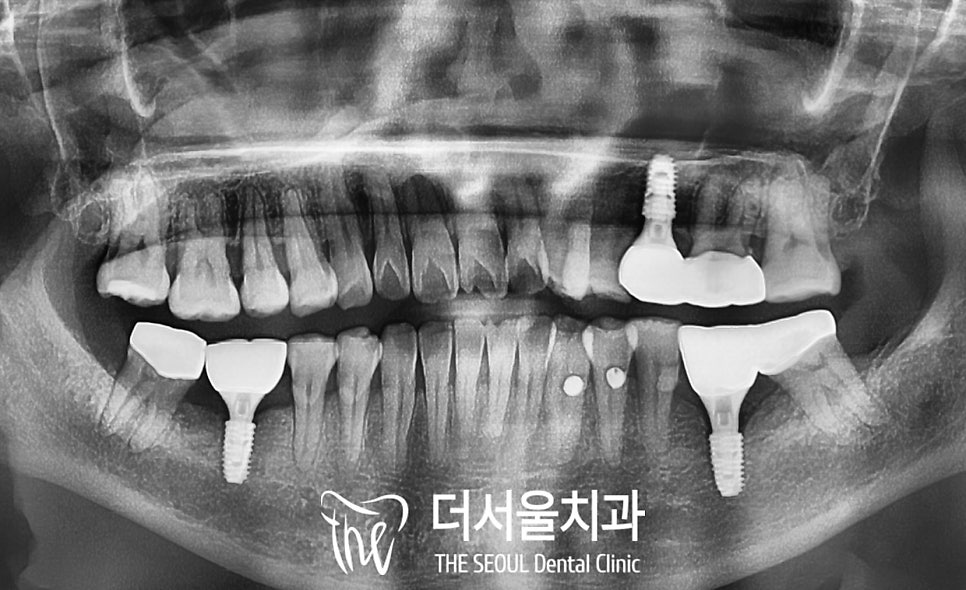

상하악의 해부학적 구조를 피해

안전하게 식립을 마친 모습입니다.

픽스처의 고정이 끝나고 나면

뼈와 단단하게 잘 붙었는지

고정력 측정기를 이용하여

수치를 확인합니다.

주변으로 하얗게 치조골이

잘 차올랐다면

맞춤형 어버트먼트 제작을 위한

본뜨기 과정과 잇몸 치유 단계를 거치고

최종 크라운을 올려드립니다.

모든 진료가 마무리 된

구강 내 모습인데요,

보철은 나중에도 더서울에서

꾸준히 유지 보수를 해줄 수 있도록

SCRP type으로 제작하였고,

우식의 범위가 넓었던 치아들은

크라운을 씌워 보호해 주었습니다.

골질의 상태에 따라

보철을 브릿지로 제작하여

저작력을 분배할 수 있도록 하였으며

초기 진단 때

플랜을 꼼꼼하게 잘 세워두었기에

기간은 4개월 안에 모두 마무리 되었습니다.